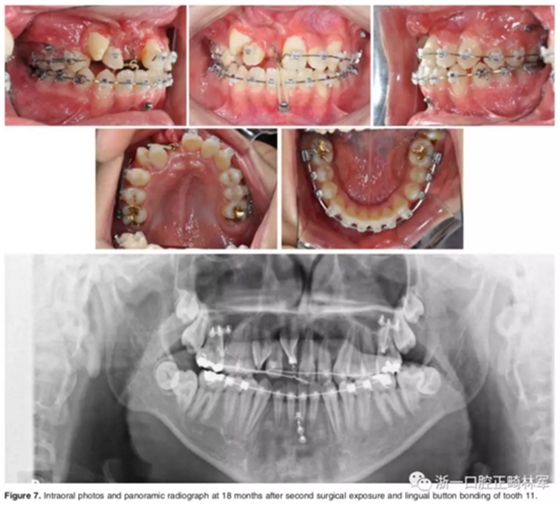

弓絲換至0.019*0.025-inch不銹鋼絲時,開始進行外科手術暴露阻生牙。由于易位情況嚴重,三維向阻擋嚴重,因此需要行兩期手術。

一期手術主要是牽引側切牙和尖牙:于上頜前牙區(qū)唇側作切口,翻全厚瓣;腭側面較小;在尖牙唇側、側切牙腭側粘扣掛結扎絲牽引,通過一輔助鈦板及樹脂等連接至弓絲上;采用閉合式導萌技術,將皮瓣復位縫合,僅結扎絲穿過粘膜;2周內軟組織得以愈合,牽引開始。先通過正畸力,近中移動側切牙,遠中移動尖牙。10個月后,阻生牙牙冠萌出,側切牙、尖牙的易位得以矯正。

二期手術主要是牽引中切牙:于上頜前牙區(qū)腭側作切口,翻全厚瓣,在切牙唇側粘扣掛結扎絲牽引;軟組織愈合后,牽引開始。為施加合適的垂直向力,在下頜前牙區(qū)放置C型管,掛橡皮筋牽引。14個月后,切牙牙冠萌出。使用mini管代替托槽,對切牙、尖牙進行矯治;矯治過程采用輕力,0.014-in鎳鈦絲。